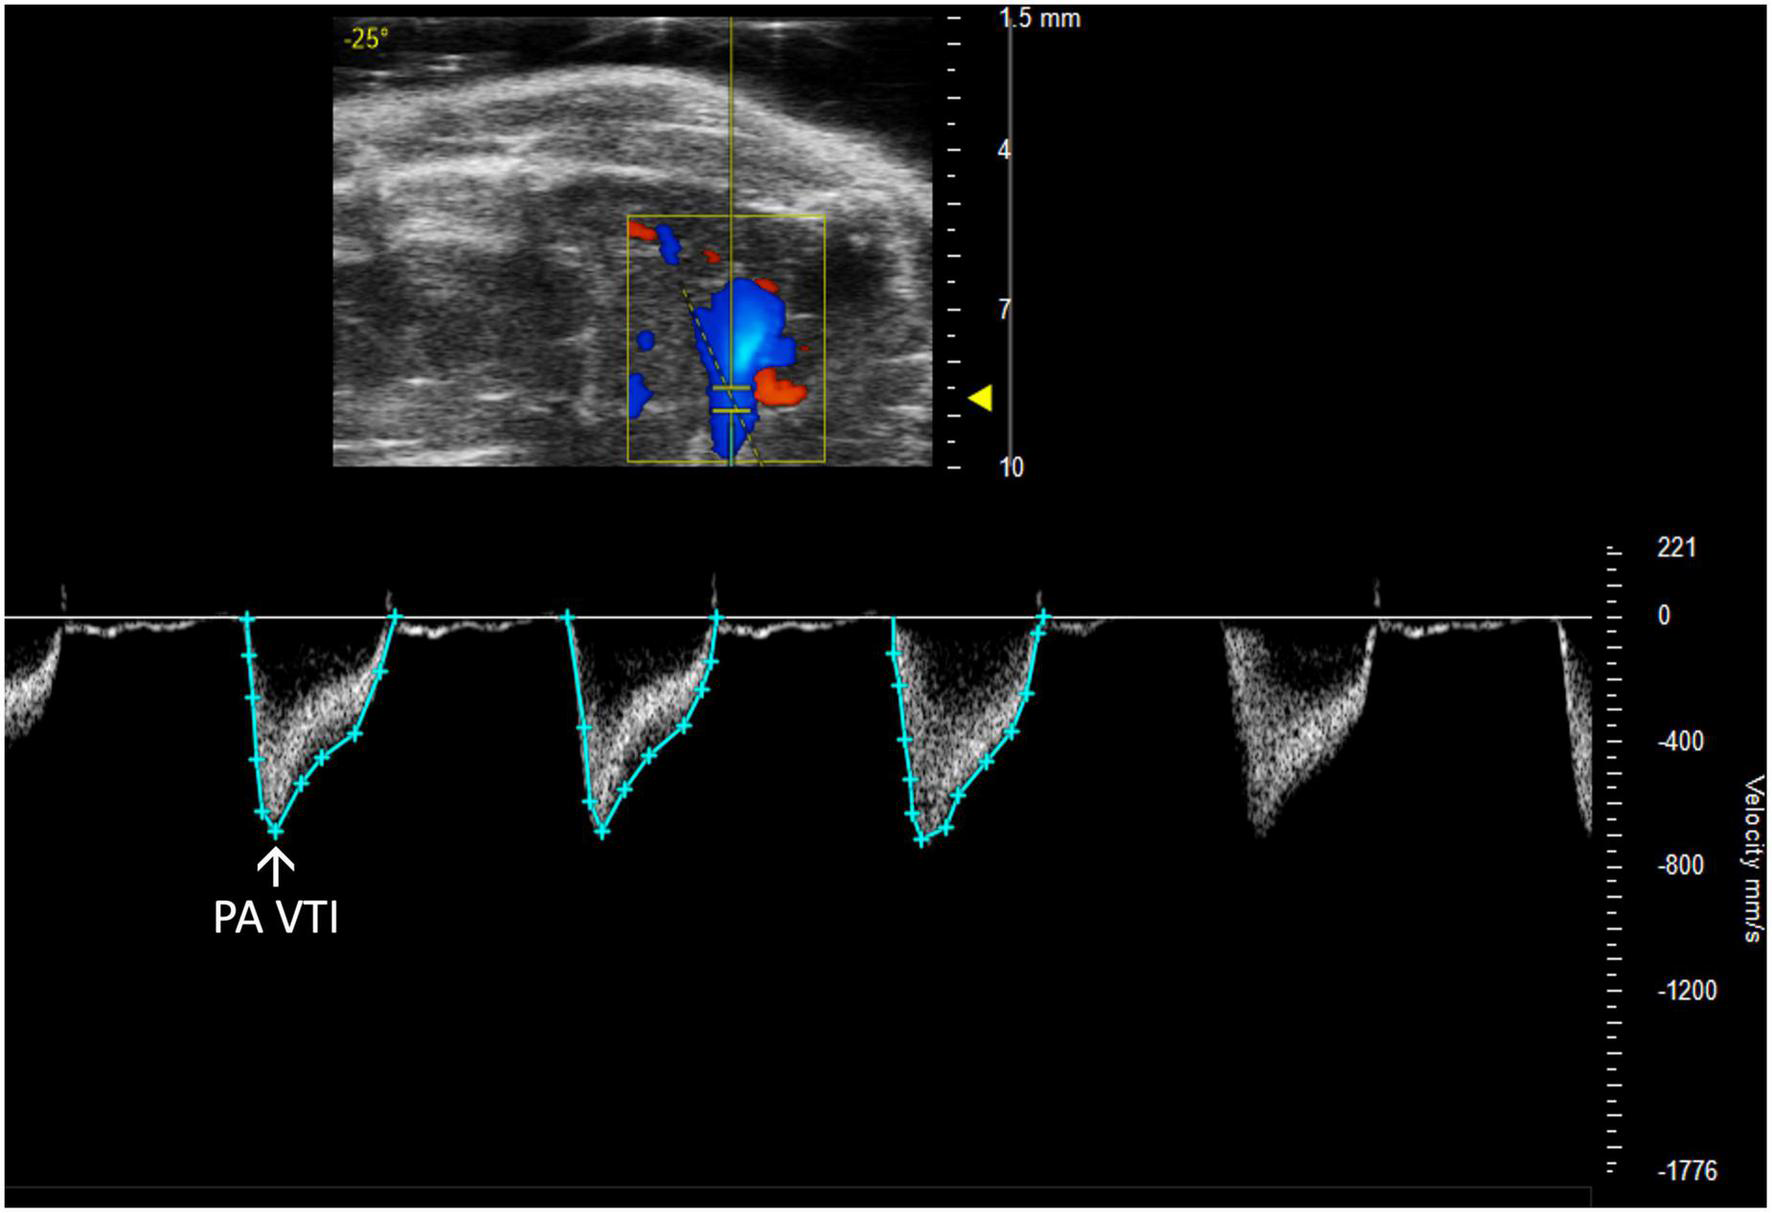

2.2.2 Pulmonary artery and valve

Pulmonary and right ventricular parameters are more informative when applied concurrently. RV dysfunction in the absence of elevated PA pressures indicates isolated RHF, while RV dysfunction concurrent with elevated PA pressures could indicate pulmonary hypertension leading to RHF or LHF leading to RHF. PA and PV measures may be incorrectly assumed to be interchangeable; however, the PA is anatomically distal to the PV in mice, and images should be captured accordingly. Measurements are made of PW Doppler mode images with the marker overlying either the PA or PV (Figures 4, 5).

FIGURE 4

Pulmonary artery velocity time integral (PA VTI) directly measures blood flow through the pulmonary artery and is acquired as the area under the curve in pulsed wave (PW) Doppler mode of the parasternal long axis (PLAX) view.

2.2.2.1 Pulmonary artery velocity time integral

Pulmonary artery velocity time integral (PA VTI) is a direct measure of blood flow through the pulmonary artery. It is calculated as the area under the curve in a PW Doppler image of the PA (Figure 4). Mean velocity, mean gradient, peak velocity, and peak gradient are automatically generated. This measure can be used to evaluate PAH because increased PA flow accompanies PAH (6).